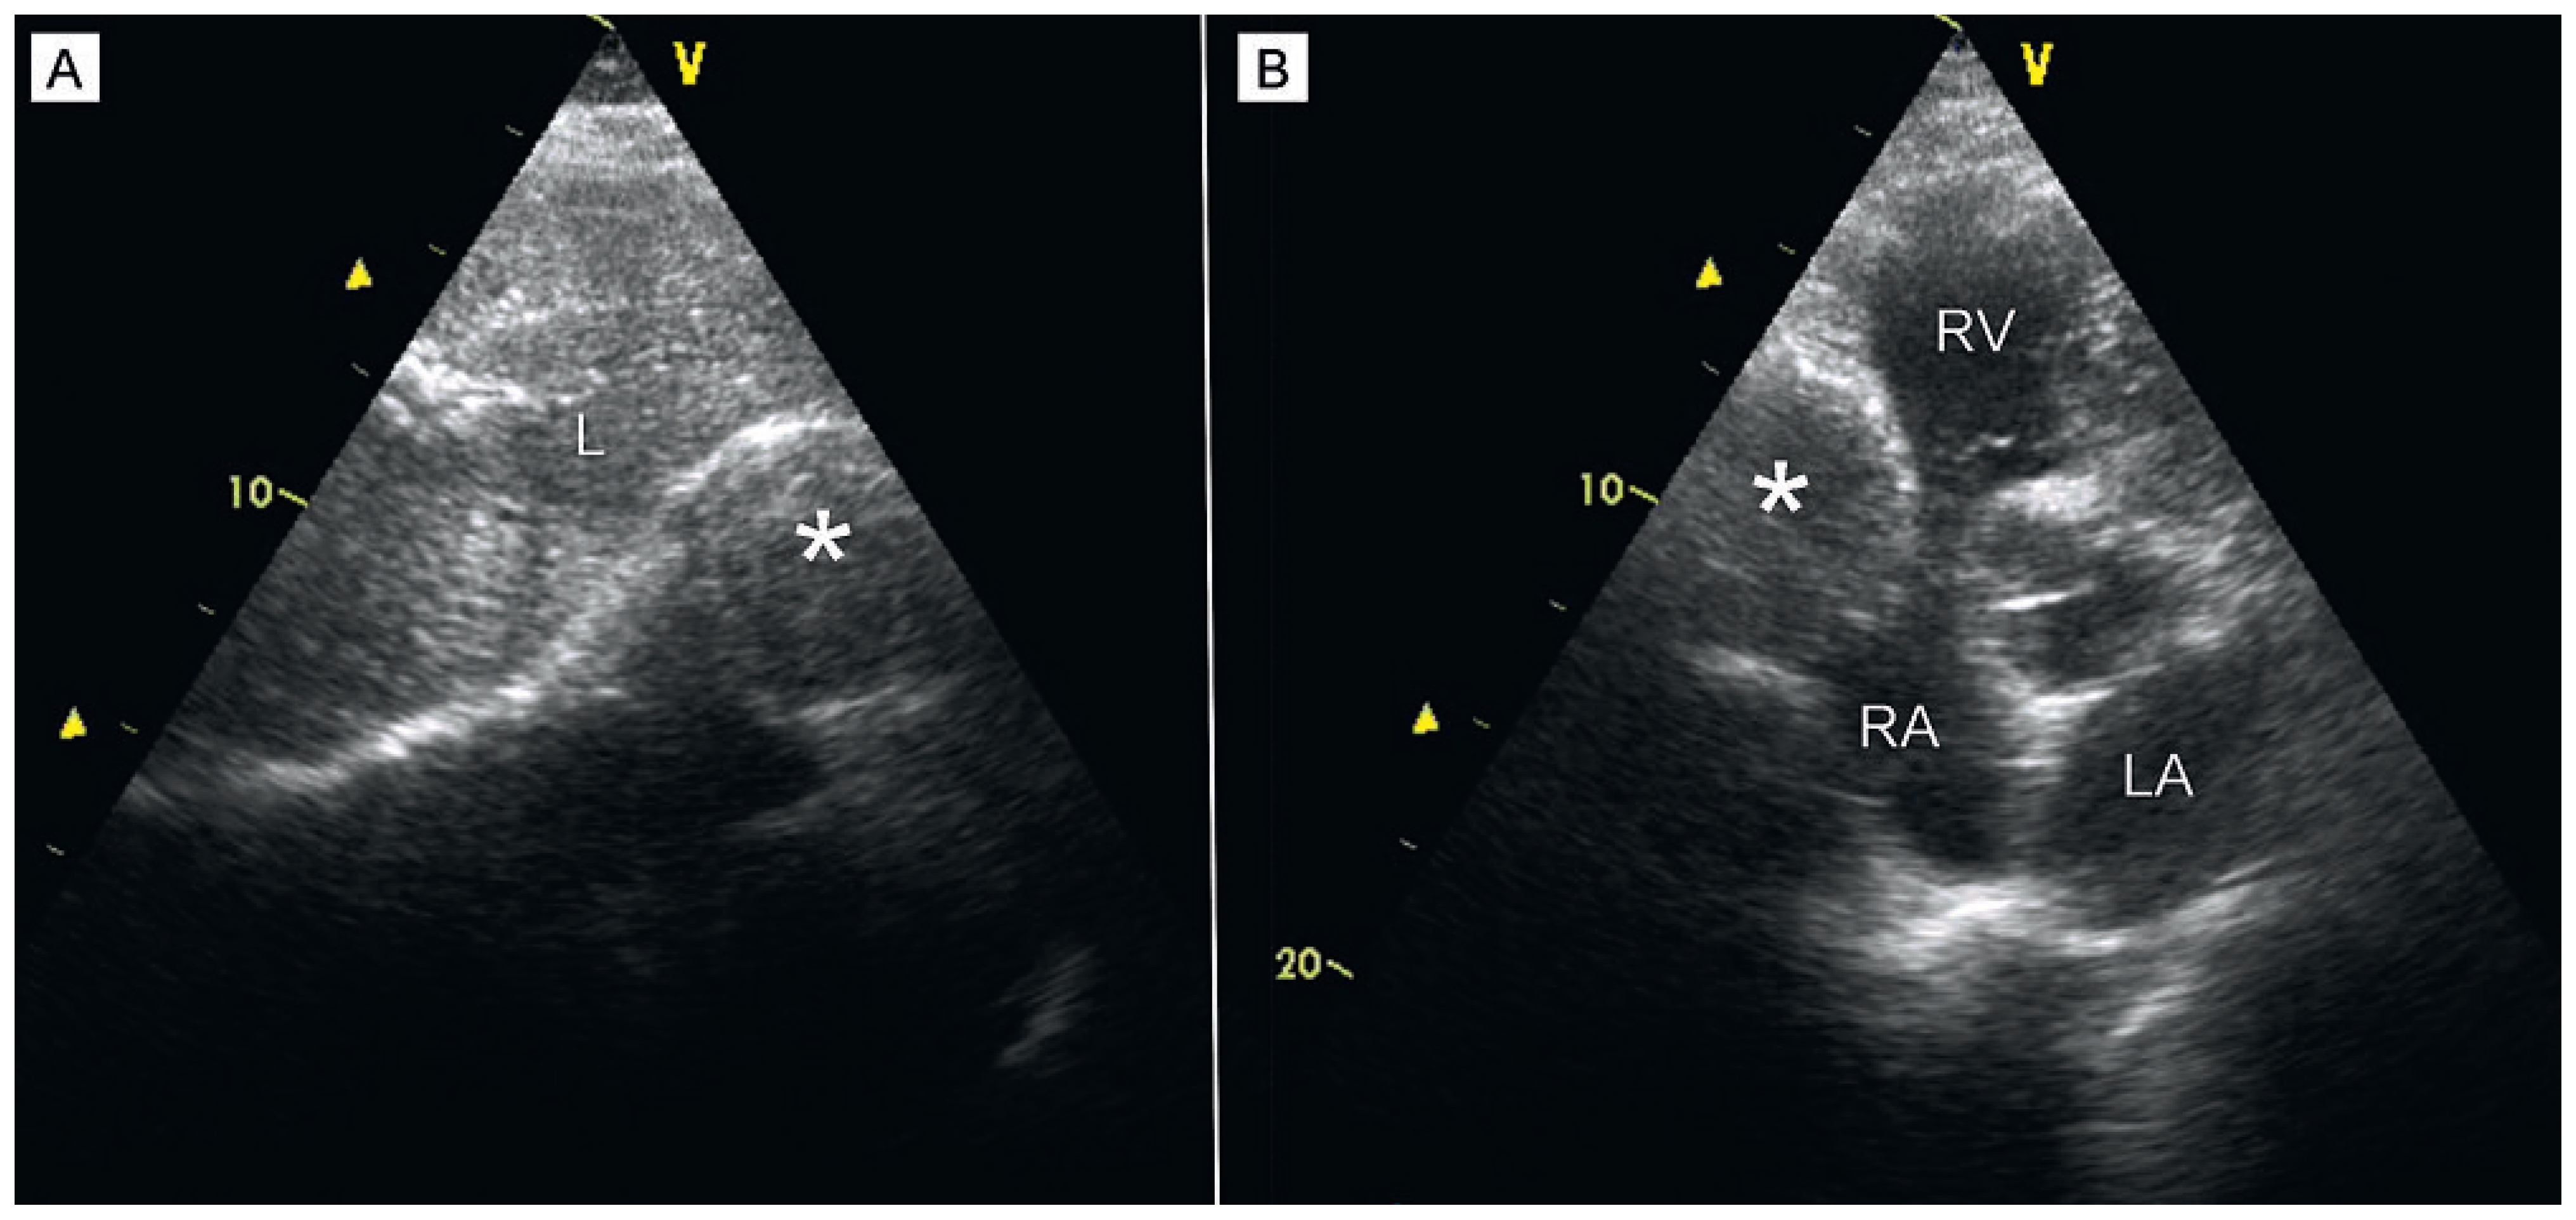

A Giant Saphenous Vein Graft Aneurysm Compressing the Right Cavities